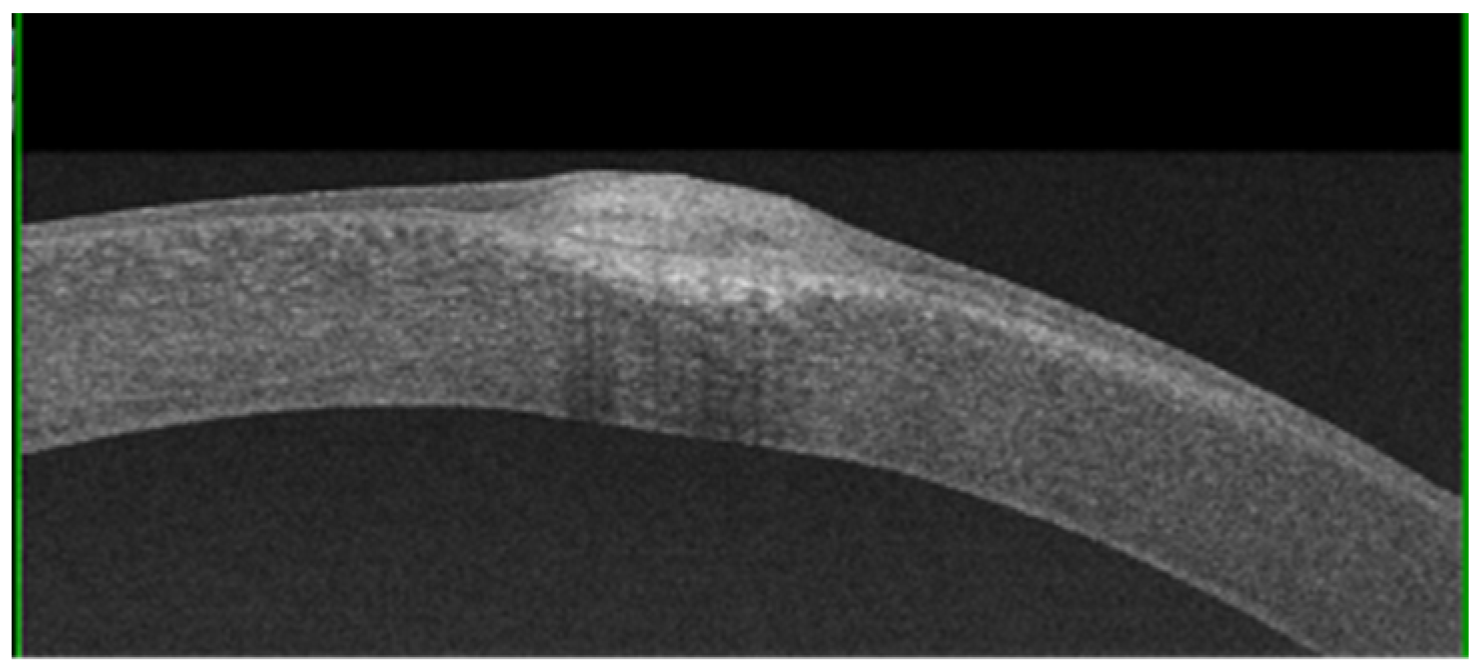

The subepithelial elevated nodules of the disease are gray-white or blue-white, and they often present in a roughly circular configuration involving the central or paracentral cornea. The nodules are typically separated by a clear cornea and are localized in the mid-periphery, and there may be only one or up to eight of them, and the nodules might be confluentin advanced stages.(Figure 1 and Figure 2). In some cases, the nodules are localized in the central cornea. This condition occurs in association with dry eye or long-standing keratitis (e.g., phlyctenulosis, trachoma, and interstitial keratitis), and the degeneration may not appear until years after the active keratitis has subsided. In extensive CL wearers, typical nodular localization at 3 and 9 o’clock has been described [5]. In about 60–68% of patients, there have been reports of symptoms such as pain, foreign body sensation, tearing and relapses in corneal erosions. In advanced stages, the most common presenting symptom is decreased visual acuity, and this is due to induced irregular astigmatism with hyperopic shift.

AS-OCT can be used to evaluate the morphological characteristics and depth of nodules, as well as their adherence to the underlying planes, in order to take decisive therapeutic choices [12,13]. AS-OCT can show some nodules with triangular spicules that protrude into the underlying space, and they are occasionally shown with a stromal scarring below the Bowman’s membrane.

Additionally, AS-OCT evaluation has proven effective in differential diagnoses with monolateral squamous neoplasia of the ocular surface and in addressing the correct therapeutic approach [14].AS-OCT shows coalescent subepithelial deposits with a variable and heterogeneous signal intensity, probably due to density fluctuations (Figure 5). The nodules are overlaid by a thinned epithelium. A structural and ultrastructural analysis of the corneal epithelium showed dramatic changes; indeed, a reduction in its height, particularly above the nodule in advanced stages, was demonstrated [15].

Figure 5. A nodule imaged via AS-OCT showing hyper-reflective deposits located under the epithelium and extending into the anterior stroma.